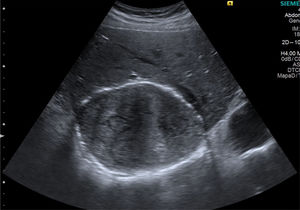

Realizamos estudio ecográfico abdominal por masa de probable evolución crónica a nivel hepático, sin alteraciones analíticas (reactantes de fase aguda negativos), ni repercusión sobre el estado general donde apreciamos 2 imágenes de características quísticas en el lóbulo hepático derecho de 13×10×9cm con zonas calcificadas y otra de menor tamaño en el lóbulo izquierdo con contenidos en sus interiores tipo vesiculiforme sugestivos de quistes hidatídicos (fig. 1). Los hallazgos ecográficos en esta entidad pueden variar desde lesiones quísticas hasta otras aparentemente sólidas. Existen varias clasificaciones, la clásica de Gharbi et al.1 de 1981 y más recientemente la de la OMS de 2003 (WHO/IWG)2 con la intención de unificar de forma sencilla el diagnóstico y el tratamiento de la hidatidosis basado en los hallazgos de las imágenes ecográficas.